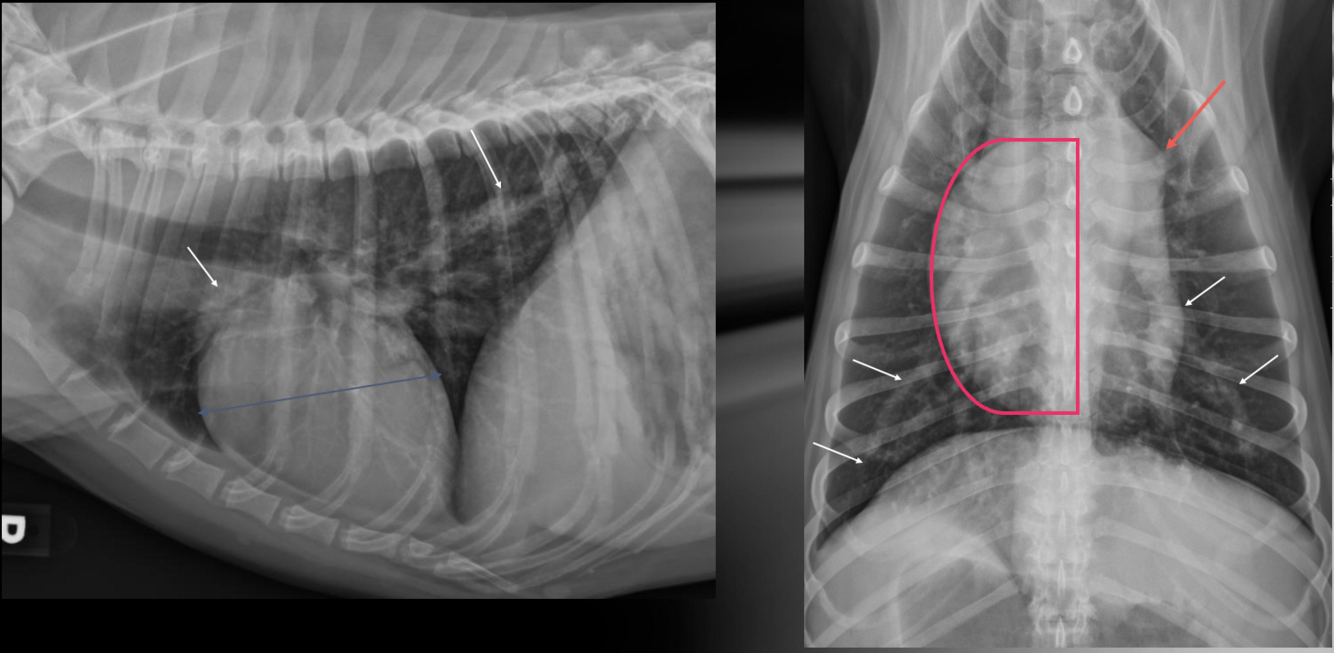

What is shown in these images?

A

pulmonic stenosis

-right heart enlargement

-main pulmonary artery segment enlargement

-possible right heart failure